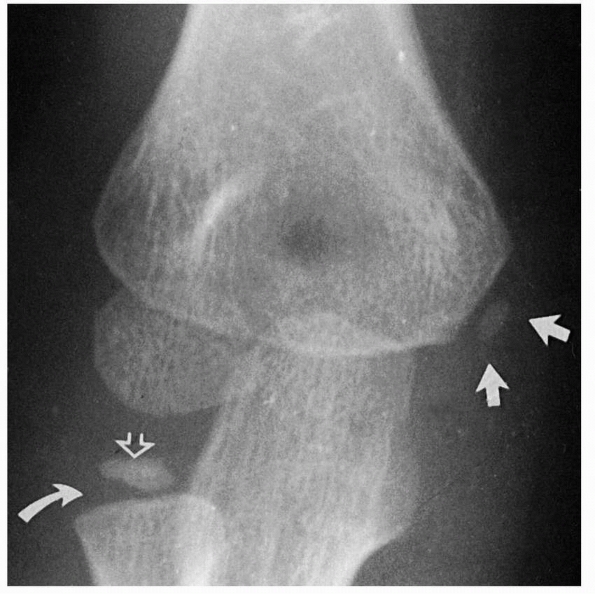

area, a medial epicondyle begins to ossify (Fig. 13-4).

FIGURE 13-4 At about 5 or 6 years of age, a secondary center develops in the medial epicondylar apophysis (white arrows). At this same time, the ossification center of the radial head also develops (open arrow). Note that the physis of the proximal radius is widened laterally (curved arrow).